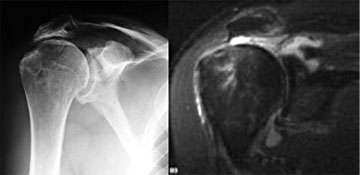

Röntgen:

Die bildgebende Diagnostik umfasst neben Röntgenaufnahmen der

Schulter in 3 Ebenen, die Aufschluss über die knöcherne

Darstellung der Schulter ergeben, die Sonographie und die Durchführung

einer Kernspintomographie der Schulter, um neben der Rupturgröße

die Qualität der Muskulatur beurteilen zu können.

|

Abbildung:

MRT einer Rotatorenmanschettenruptur |